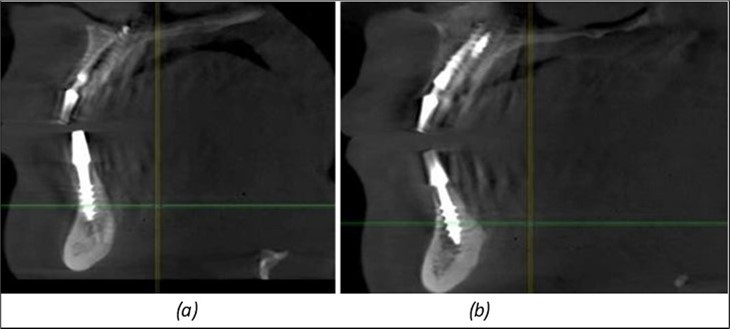

Figure 13.Corticobasal BCS implants fixed between the vestibular and lingual cortices with support on the basal bone: (a) BCS fixed between the lateral cortices; (b) BCS implant with support on the basal cortex.

In the interforaminal area (Figure 3, Figure 13), 6 corticobasal implants are also placed. The increased number of implants is due to the poorly represented distal area that needs to be compensated.